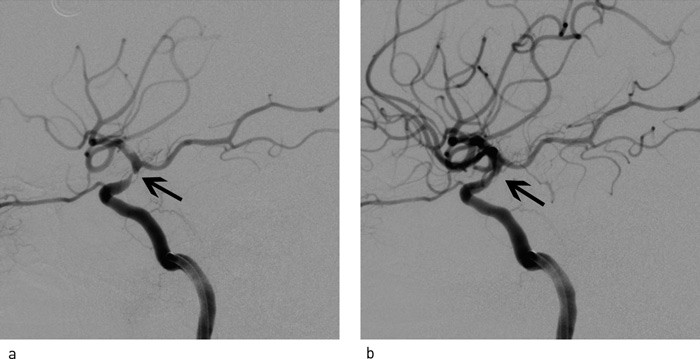

Ved cerebral angiografi ble det påvist akutt okklusjon av distale del av a. carotis interna på venstre side (carotis terminus) (fig 3a), manglende fremstilling av bakre a. comunicans posterior samt tynn første gren av høyre a. cerebri anterior. Begge carotisbifurkasjoner på halsen var normale. Ved hjelp av et trombektomikateter (MERCI-slynge, Concentric Medical Mountain View, California) ble venstre a. carotis interna, media og anterior åpnet opp (fig 3b, 3c, fig 4a, 4b). Blodgjennomstrømmingen til venstre hemisfære ble med angiografi verifisert gjenopprettet nesten tre og en halv time etter symptomdebut. Umiddelbart etter var pasienten noe mer våken og kunne med noe møye si navnet sitt (NIHSS 14). CT av hodet viste ingen blødning, men ødem i venstre hemisfære. CT dagen etter viste lavattenuerende forandringer i deler av a. cerebri medias forsyningsområde på venstre side. Han lå i flere dager i intensivavdeling. Ny vurdering angående hemikraniektomi ble aldri nødvendig. Pasienten ble overført til opptrening i slagenhet, der han fire uker etter prosedyren var i klinisk bedring.